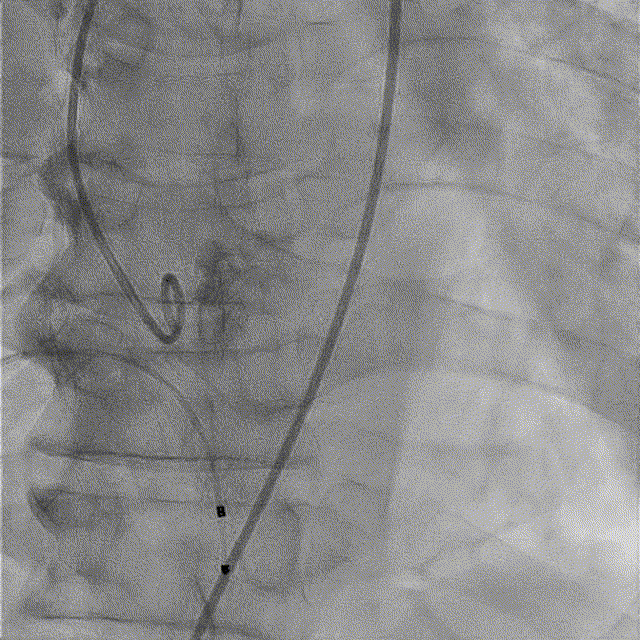

TaurusNXT植入过程

全麻后超声引导下建立入路,左侧股动脉置入TaurusNavi 20F血管鞘。跨瓣后左室放置Lunderquist导丝,使用TaurusAtlas 20mm球囊预扩,球囊无明显位移,有轻微腰征、无漏。输送系统预备同侧Snare从右股动脉送入,安全顺利通过主动脉弓。瓣膜在双窦展开位约瓣上2mm位初始定位释放,工作位造影多角度评估后予以释放(一次定位释放,未采用多次回收功能)。超声下显示瓣膜偏椭圆,之后使用TaurusAtlas 22mm球囊后扩,支架形态改善明显,导管测压由术前的70mmHg即刻下降至1mmHg,术后即刻超声心动图评估显示瓣膜位置良好,微量瓣周漏,血流动力学指标理想。

术中影像

主动脉根部造影

球囊预扩

预备Snare跨瓣

瓣膜初始定位

工作位造影(双窦展开位)

完全释放

球囊后扩

最终造影